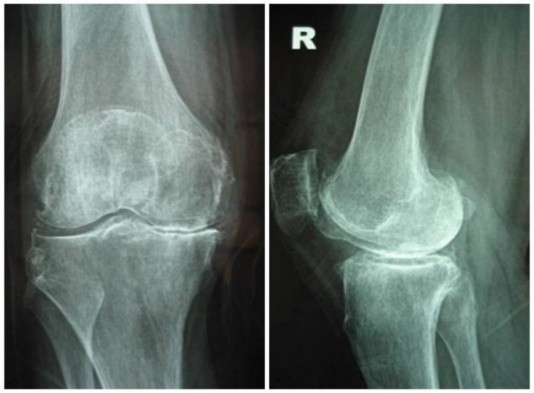

Thoái hóa khớp là tình trạng tổn thương sụn khớp và xương dưới sụn, kèm theo phản ứng viêm và giảm dịch khớp.

Thoái hóa khớp khởi phát từ sự mất cân bằng giữa quá trình tổng hợp và thoái giáng của sụn khớp. Các Cytokine tiền viêm như IL-1 và TNF- kích thích men tiêu protein (MMPs) phá hủy lưới Collagen tuýp II và Proteoglycan, làm trơ sọi xương dưới sụn, gây đau và biến dạng.

- Vị trí: Thường gặp ở khớp gối, khớp háng, cột sống thắt lưng và các khớp ngón tay.

- Biến dạng khớp: Sưng to, lệch trục, teo cơ….